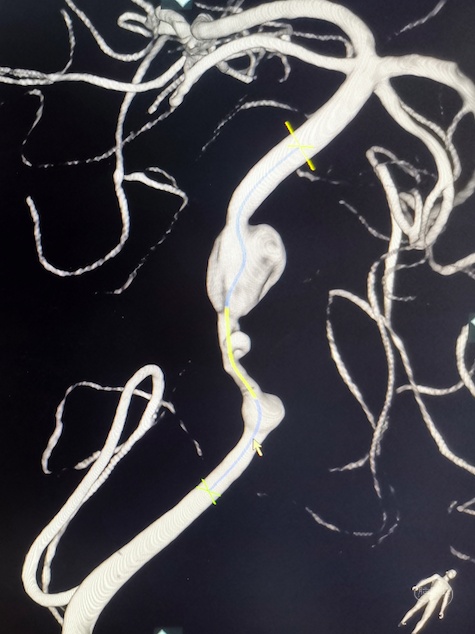

3D重建显示基底动脉下部、双椎结合部、左椎多发夹层动脉瘤:

双抗5天后行左侧椎动脉多发夹层动脉瘤Pipeline™ Flex 血流导向密网支架植入术。

Pipeline™ Flex 血流导向密网支架 PED-325-35